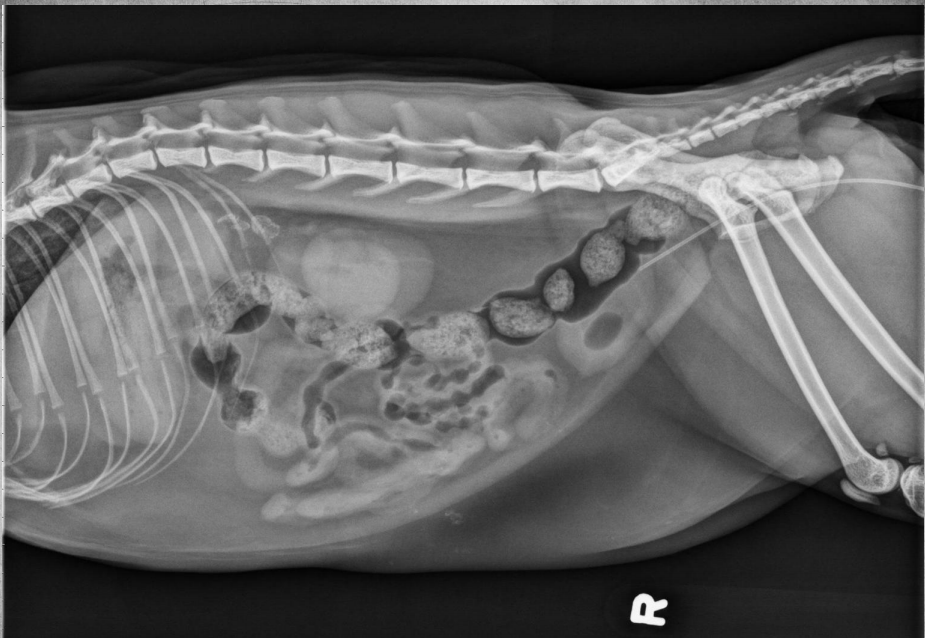

●9 yo mixed breed female dog

(sterilized)

●Increased ALP

● Impressive amount of subcutaneous and intra-abdominal fat.

● Enlarged liver – changed gastric axis pushed caudally, rounded edges, extending past the costal arch.

● At least two round soft tissue opacity structures superimposed on ventral liver (lateral view).

● Round soft tissue structure cranial to right kidney.

● Mass in adrenal gland or pancreas

● Hepatic nodules (benign vs metastatic disease)

SI gas is normal because bowels empty.